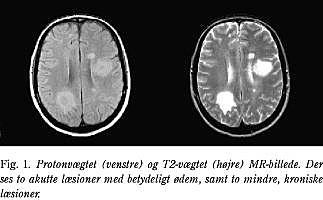

Akutte og kroniske MS-læsioner er hyperintense på T2-vægtede og protonvægtede billeder (Fig. 1). Det samme er tilfældet for de fleste andre patologiske forandringer som for eksempel inflammatoriske, infektiøse eller neoplastiske forandringer. Hyperintensiteten skyldes blandt andet øget vandindhold, hvilket ses ved både ødem, demyelinisering, remyelinisering, gliose og axontab.